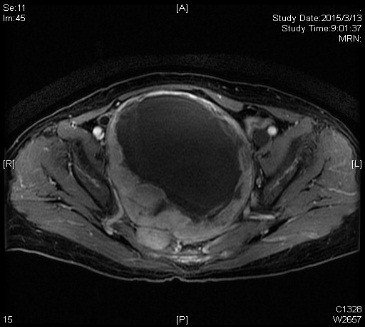

经进一步术前检查发现,尚女士肿瘤位于盆腔内,大小约25*20*20cm,瘤蒂位于右侧骶1-2骶前孔,部分实性成分位于右半骶骨内,在骶孔中塑形生长,手术暴露困难;瘤周异常血管网丰富,与髂总及髂内血管及骶前静脉丛毗邻,术中极易发生难以控制的大出血。不仅如此,肿瘤邻近膀胱、子宫及直肠,周围脏器易受损伤;右侧输尿管下段受到肿瘤压迫,右肾积水征象明显。为确保手术的安全性,术前神经外科、普外科、泌尿外科、血管外科等多名专家对病例进行了多学科讨论。血管外科吴巍巍主任指出,为预防术中发生大出血可考虑先予以腹主动脉球囊阻断,多次与患者及家属沟通,遗憾的是患者及家属拒绝预先行阻断手术,术中出血的风险再次增加。